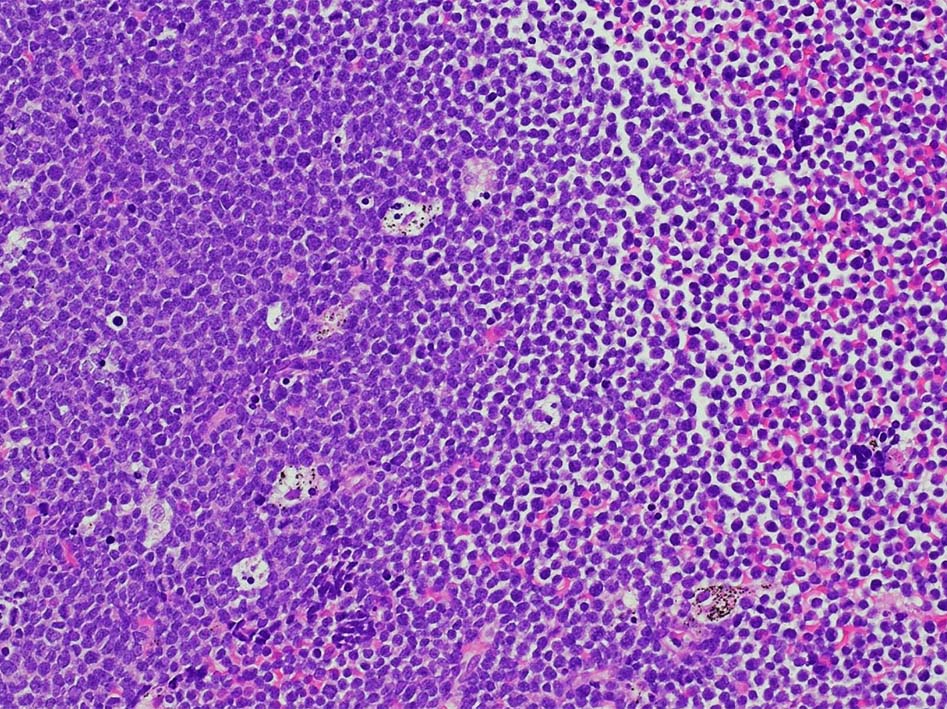

T-lymphoblastic leukaemia/ lymphoma

Tリンパ芽球性白血病/リンパ腫、NOS( WHO5th classification*1)

慣例では、末梢血および骨髄が主要病変部位である場合は白血病(T-ALL), リンパ節、胸腺またはその他の結節外部位が主要病変部位である場合はリンパ腫(T-LBL)という用語を使用する。

Tリンパ芽球性白血病とTリンパ芽球性リンパ腫の区別は、臨床像および骨髄浸潤の程度に基づいて行われる。白血病は、末梢血および/または骨髄に著明な浸潤を認める疾患(通常、骨髄芽球25%以上とみなされる)を指すのに対し、リンパ腫は、胸腺、リンパ節または節外部位への浸潤を含む、組織ベースの腫瘤性病変を指し、末梢血または骨髄への浸潤はないか、あってもごくわずかである*2。 末梢血/骨髄の浸潤と腫瘤性病変の両方がある場合は、有意な区別はない。一般に、両者には生物学的および臨床的に大きな重複があり、WHOの分類スキーム(WHO4th rev Ed 2017)によれば、臨床像の異なる同一疾患とみなされる。

T-ALL/LBL 縦隔腫瘍, 胸水貯留症例

70歳男性 KNS

右肺上葉から前縦隔に90mm大の腫瘤あり. 右胸水貯留を伴う. 右主気管支よりEBUS-TBNAをおこなう.